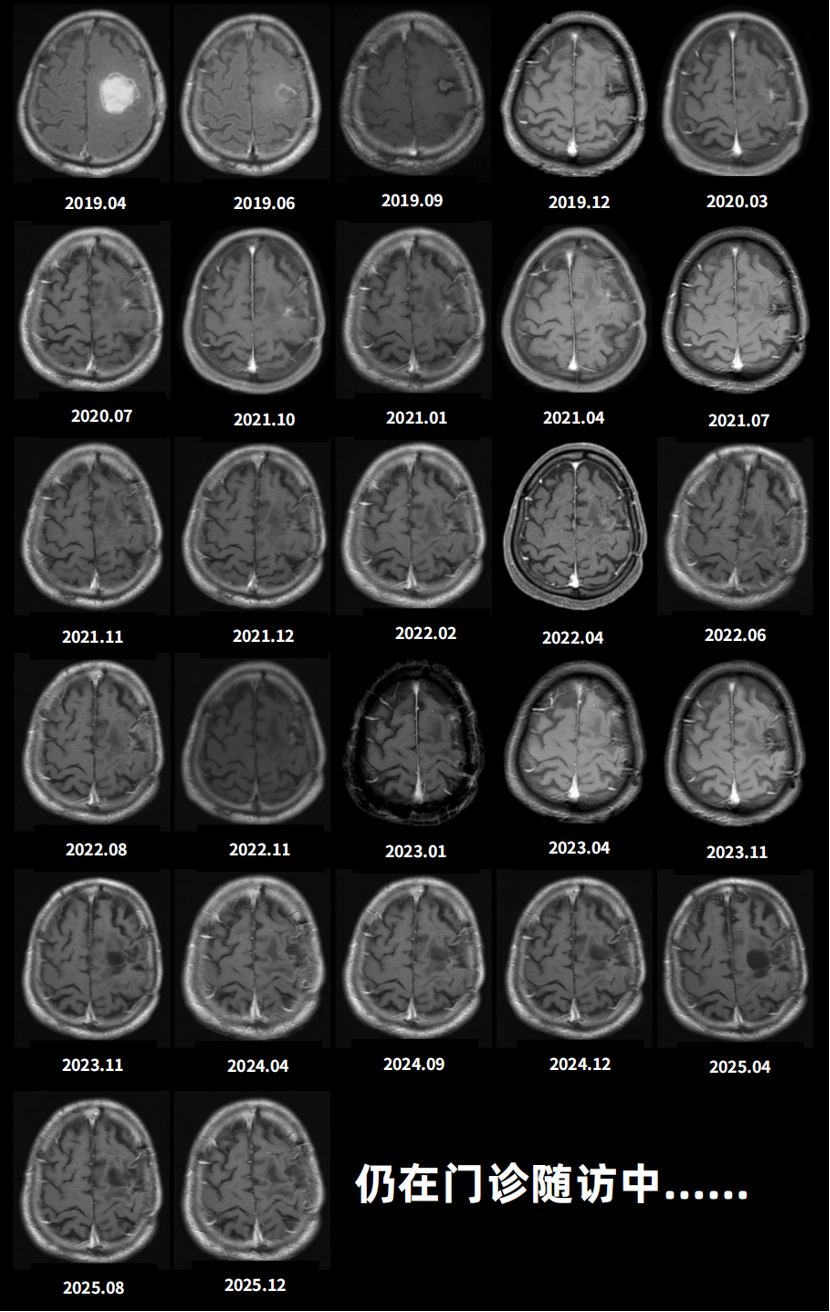

后续治疗期间,定期每2-3个月门诊复查头部增强MRI扫描(图6)。2022年8月首次提示可疑复发,11月复查确认,遂再次启用TMZ化疗,继续采用5/28方案,每周期连续服药5天,共完成12周期。截至2026年2月27日随访,影像学显示肿瘤未见复发,生存时间超过7年。患者目前KPS评分90分,生活可自理,行走稳定,坚持早睡早起及适量运动,心态积极乐观,整体状态良好。

图5.患者术后门诊定期复查MRI影像